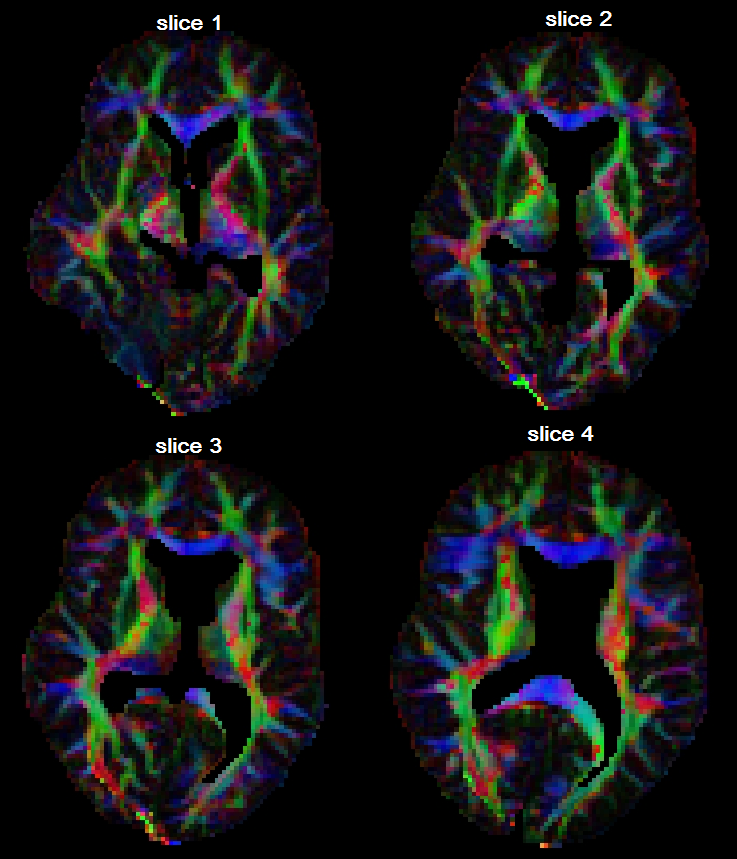

Diffusivity profiles

Fig. 8 shows the diffusivity profiles based on the posterior estimates of the tensors at all voxels in a region of interest. For each direction and spatial location , we plot the point , where is the posterior expectation of the diffusivity. In order to observe the differences between 2nd and 4th order tensor models, in Fig. 9 we zoom into the ROI (a) and (b), and see that the 4th order tensor model captures the fiber-crossings which the 2nd order model cannot capture. At the fiber-crossing locations, under the 2nd-order model the two largest eigenvalues of the estimated tensor have similar sizes, with a donut-shaped diffusivity profile.